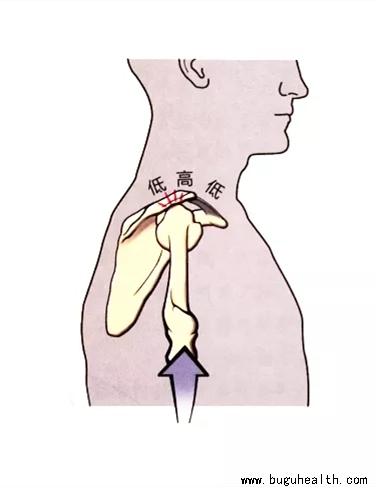

- 为了获得全范围的外展运动,肱骨大结节必须在远离肩峰下表面的位置;可以通过肩关节外旋或在肩胛骨平面进行外展来实现。为了说明这一点,首先尝试进行冠状面的外展,手臂充分内旋(腋指指向下方),然后处于中立位(手掌朝下),最后充分外旋(拇指指向上方)。内旋位时的活动范围受限是由于大结节撞击肩峰。如果肩关节外旋.....